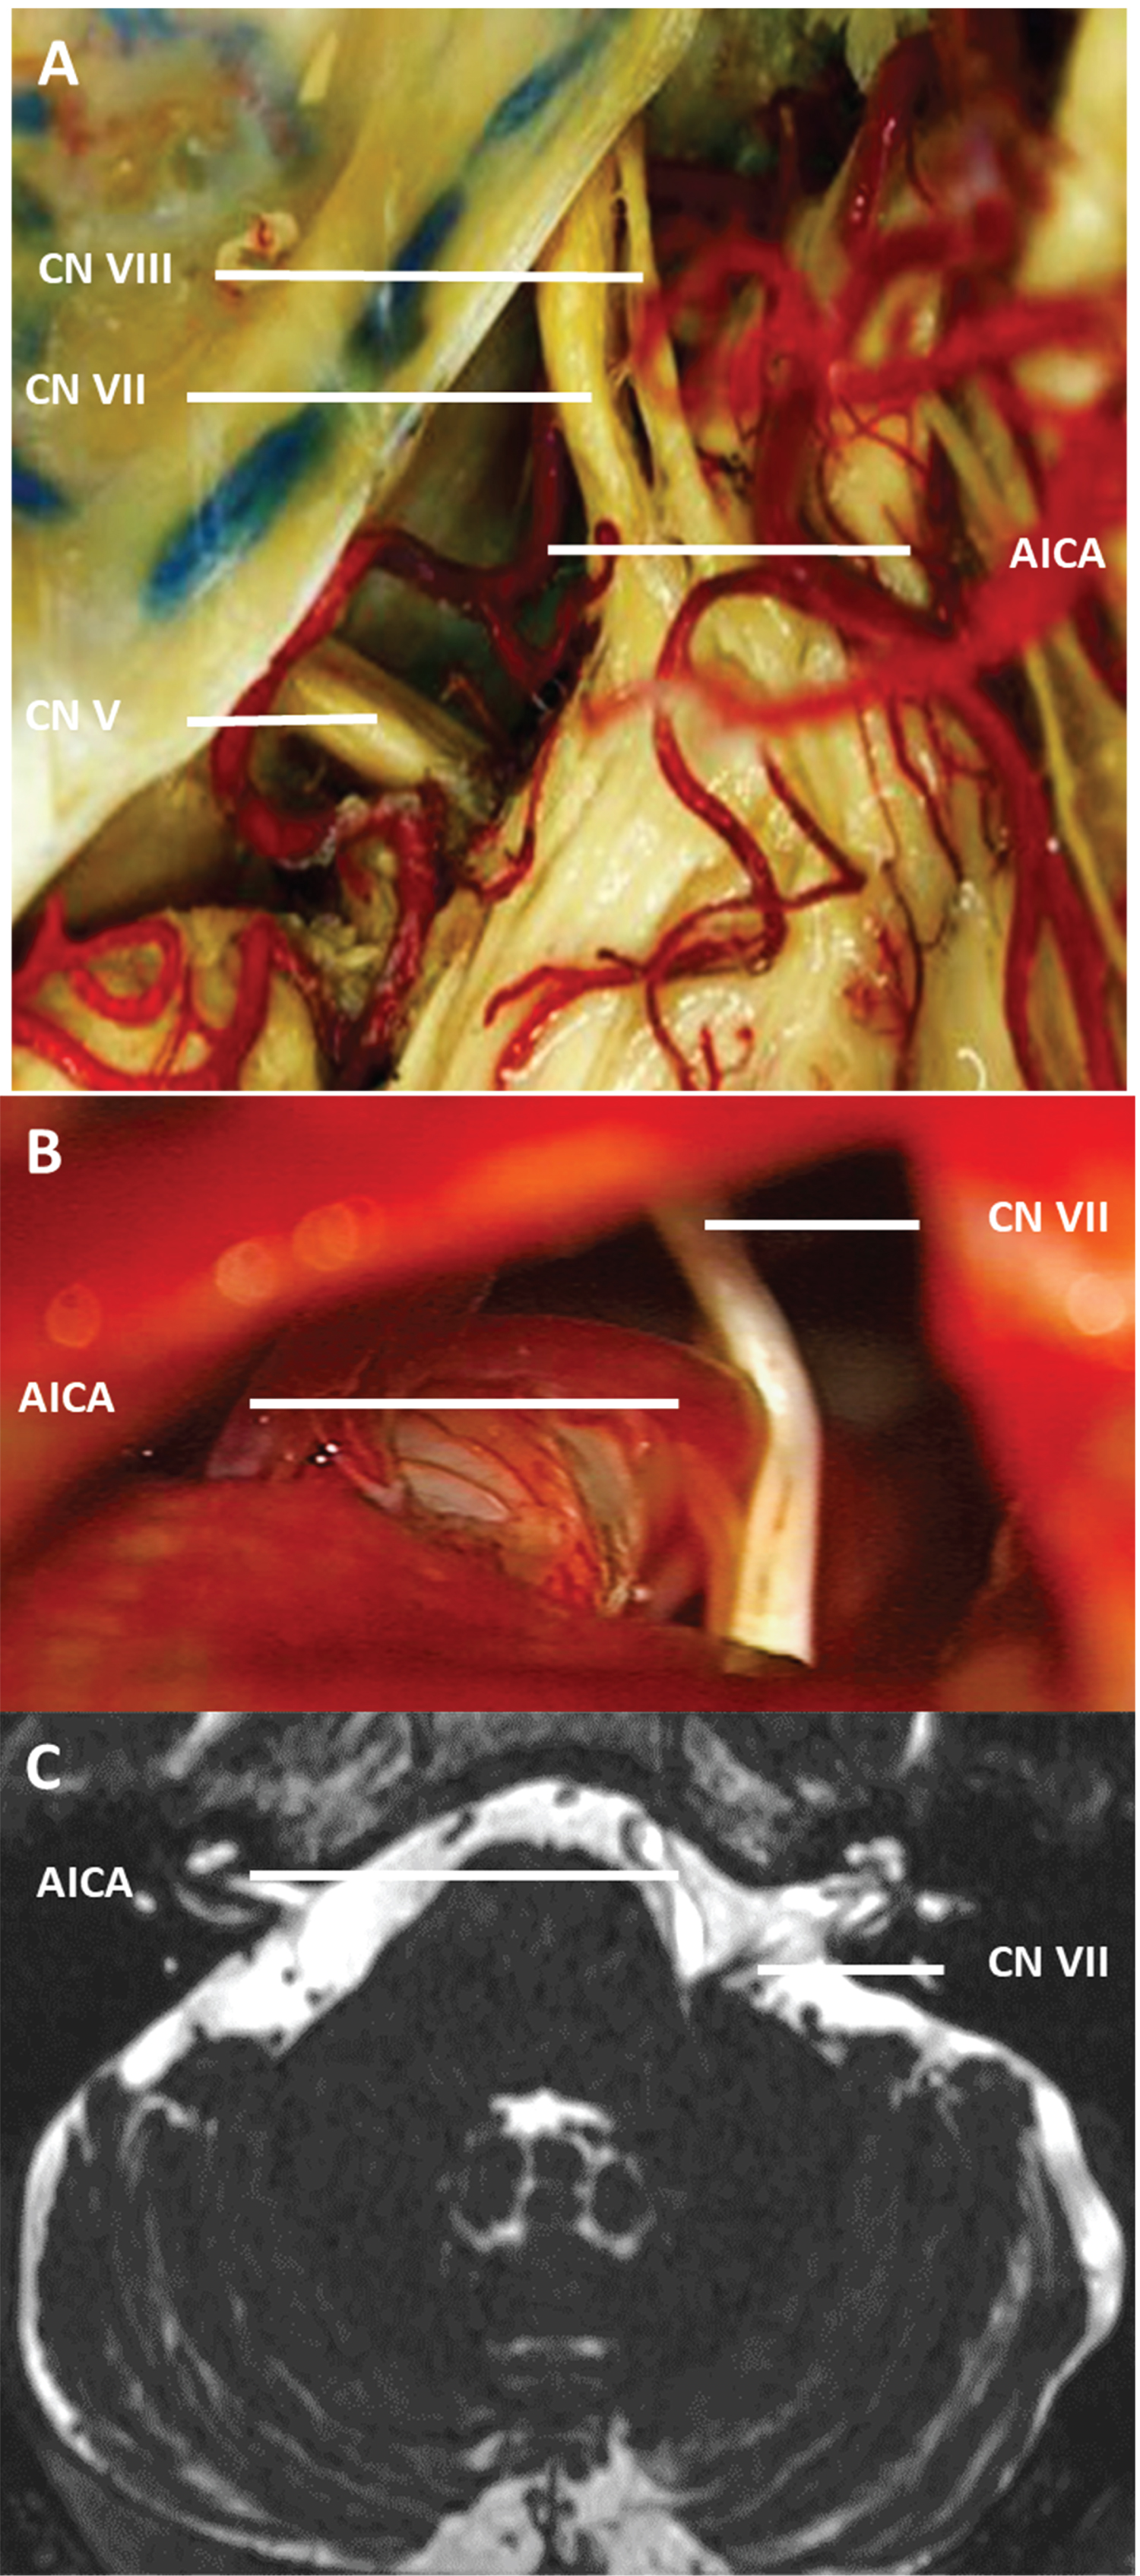

Figure 2: AICA is the most common compression on the facial nerve (A) Anatomical relationship between CN VII and AICA is shown in the cadaver dissection images; (B) Compression by AICA from the inferior part of the nerve is visible in the intraoperative image; (C) Preoperative CN VII and AICA compression image in axial T2 MRI sequence is shown.

AICA: Anterior inferior cerebellar artery; CN: Cranial nerve; MRI: Magnetic resonance imaging.

A total of 39 patients had AICA compression involving the following compression: inferior compression in 24 (61.5%) patients, anterior compression in 7 (17.9%) patients, anteroinferior compression in 4 (10.2%) patients, anterosuperior compression in 1 (2.5%) patient, medial compression in 1 (2.5%) patient, posteroinferior compression in 1 (2.5%) patient, and posterior compression in 1 (2.5%) patient; no compression was noted from the superior and posterosuperior the part of the nerves (Figure 5). These AICA compressions were subdivided into three types, excluding those involving the anterosuperior, medial, posteroinferior, and posterior compression: Type 1 (inferior compression, 61.5%), which was further classified as Type 1a (the most common and classic form, n = 18, 75%) and Type 1b (accompanied by the superior artery compression, n = 6, 25%); Type 2 (anterior AICA compression, n = 7) with Type 2a (unilateral compression, n = 5, 71.4%), and Type 2b (bilateral compression, n = 2, 28.5%); and Type 3 (anteroinferior compressions, n = 4, 10.2%).